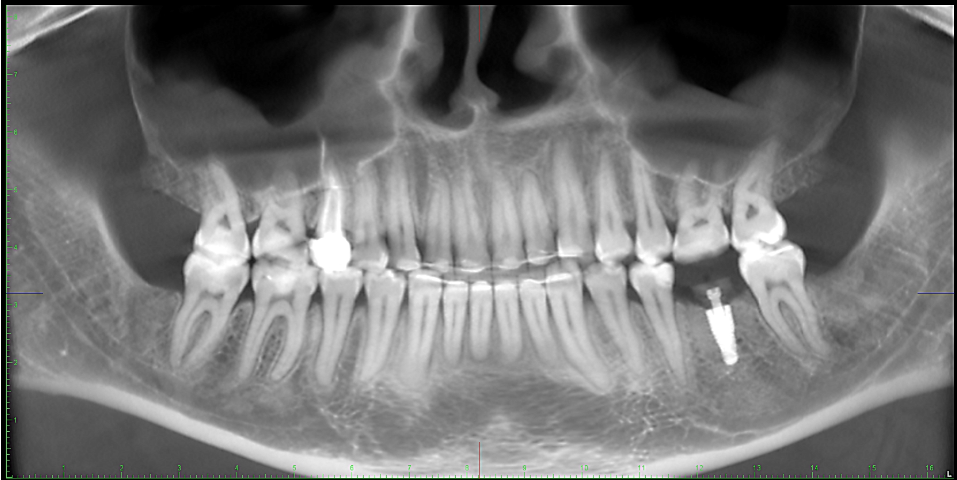

Женька Опубликовано 7 января, 2025 Поделиться Опубликовано 7 января, 2025 Такая вот имплантация получилась. История банальная. ЛКШВ, плохой фит мк-коронки, ортопед с терапевтом ревизируют и отправляют ко мне. Положение фрезы мезио-дистальное неверное. А всё потому, что сам создал себе проблем. Решил вырезать кусочек перегородки и заклинить в области лунки одного и корней (при удалении получил небольшой отлом). Вырезал, заклинил, начал препарировать ложе и понимаю, что первичную стабильность не могу получить... ещё как назло имплантат не тот, что планировал заказали к операции, пришлось брать из бокса более-менее подходящий (вместо 13мм прислали 16, а поставил 10 с чём собственно и связываю низкую стабильность, тк "топить" его для торку не хотелось). В общем пришлось выкручиваться, чуть глубже ложе, чуть другая позиция и торк в 25 всё-таки получен. ССТ с бугра и вид на 7 сутки со швами и без. Красиво получилось вроде) Даже сам доволен 8 2 3 Ссылка на комментарий

Женька Опубликовано 2 марта, 2025 Автор Поделиться Опубликовано 2 марта, 2025 @Doctor Vlad Спасибо! Ну, то что на фотках это же только было-стало) а по факту, первая позиция, она же на фото, была не верная, пересверливался и разбил перегородку. Но торк, тем не менее, получил) Губку не изолировал. Белый формик - это родное решение у Неодент. Формики 5.5 и 7.0 только из PEEK. И мне они нравятся меньше, чем титановые у корейцев, например. @Estes ССТ же подшивал, всё в тексте. Ссылка на комментарий